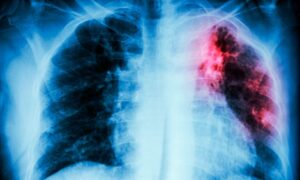

La tuberculosis es una enfermedad bacteriana infecciosa, potencialmente grave, que afecta principalmente a los pulmones.